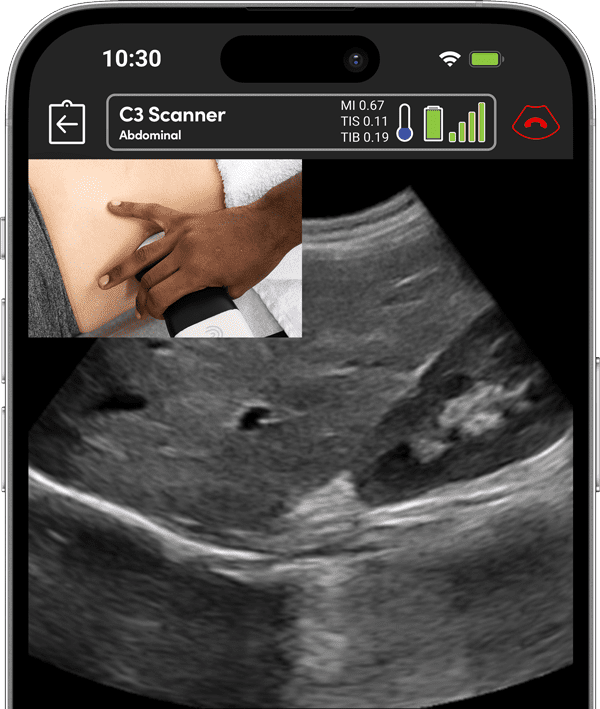

When every second counts, trained EMS professionals rely on Clarius high-definition wireless ultrasound to expedite diagnosis and triage, support pre-hospital care, and save lives.

As an emergency medicine physician in the United States I have found its image quality and functionality meets all of our highest standards there.